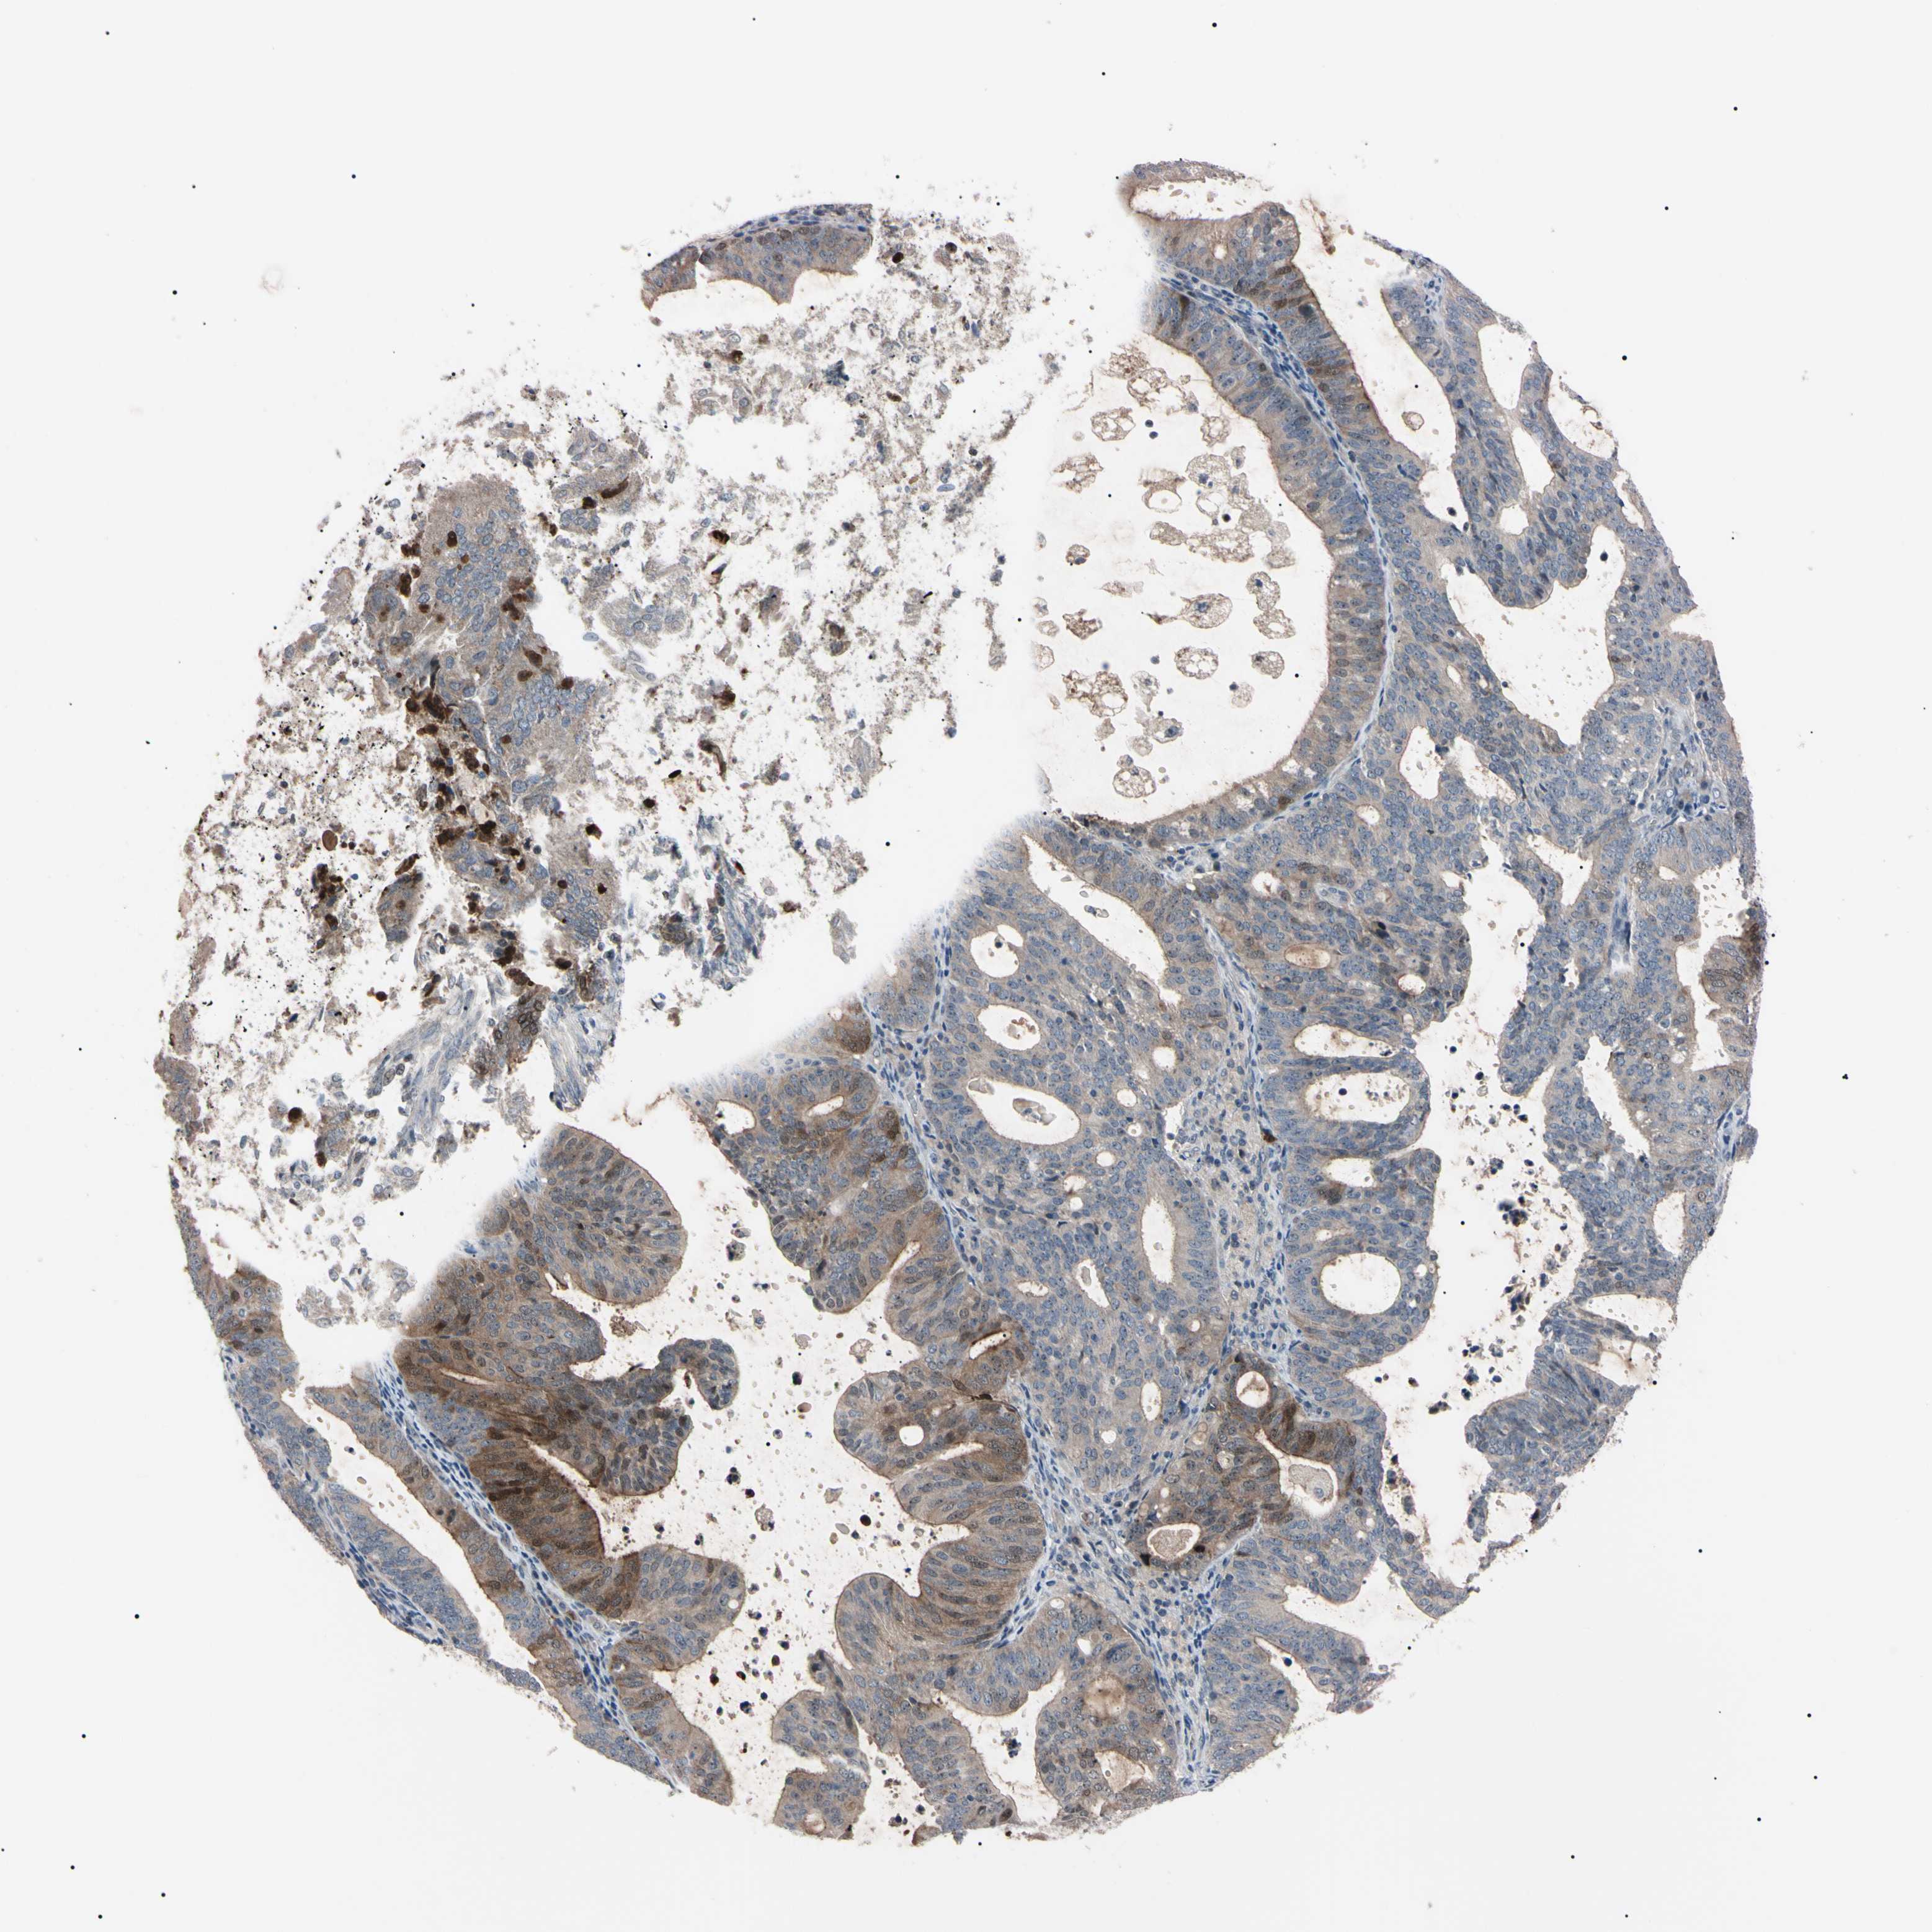

ENDOMETRIAL CANCER - Protein expressioni

A mouse-over function shows sample information and annotation data. Click on an image to view it in a full screen mode. Samples can be filtered based on level of antibody staining by selecting one or several of the following categories: high, medium, low and not detected. The assay and annotation is described here.

Note that samples used for immunohistochemistry by the Human Protein Atlas do not correspond to samples in the TCGA dataset.

Antibody stainingi

Antibody staining in the annotated cell types in the current human tissue is reported as not detected, low, medium, or high, based on conventional immunohistochemistry profiling in selected tissues. This score is based on the combination of the staining intensity and fraction of stained cells.

Each image is clickable and will lead to virtual microscopy that enables deeper exploration of all samples and also displays staining intensity scores, fraction scores and subcellular localization as well as patient and tissue information for each sample.

Antibody HPA008052

Antibody CAB010277

Staining

High

Medium

Low

Not detected

Intensity

Strong

Moderate

Weak

Negative

Quantity

>75%

75%-25%

<25%

None

Location

Nuclear

Cytoplasmic/membranous

Cytoplasmic/membranous,nuclear

Adenocarcinoma, NOS